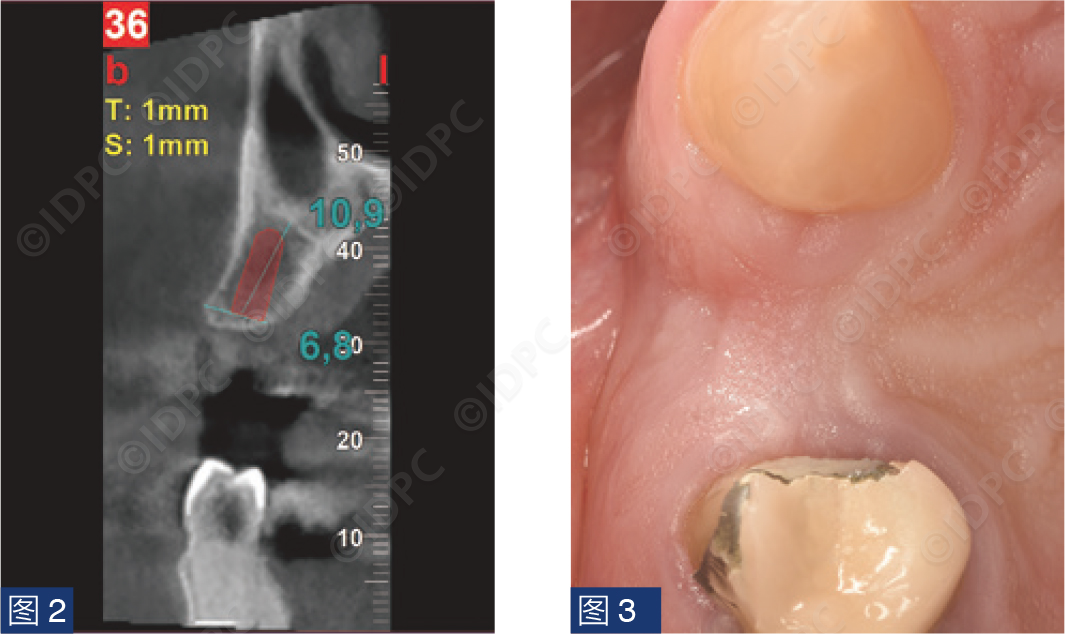

一名年轻患者主诉单端桥桥体折断(图1)。缺失的第一前磨牙满足种植修复条件。进行锥形束计算机断层扫描(CBCT),使用NNT浏览器(NewTom)进行骨量评估,并计划植入copaSKY 4 x 10 mm植体(bredent medical公司)(图2)。软组织评估显示Seibert 1级缺损(图3)。因此,采用腭侧卷曲瓣技术,植入种植体的同时补偿颊侧软组织塌陷。测量垂直向软组织厚度(图4)并计划种植体植入牙槽骨下,以便在经牙槽嵴愈合期间建立良好的生物学宽度。

图2:通过CBCT数字化完成植体尺寸设计。

图3:颊侧软组织缺损。